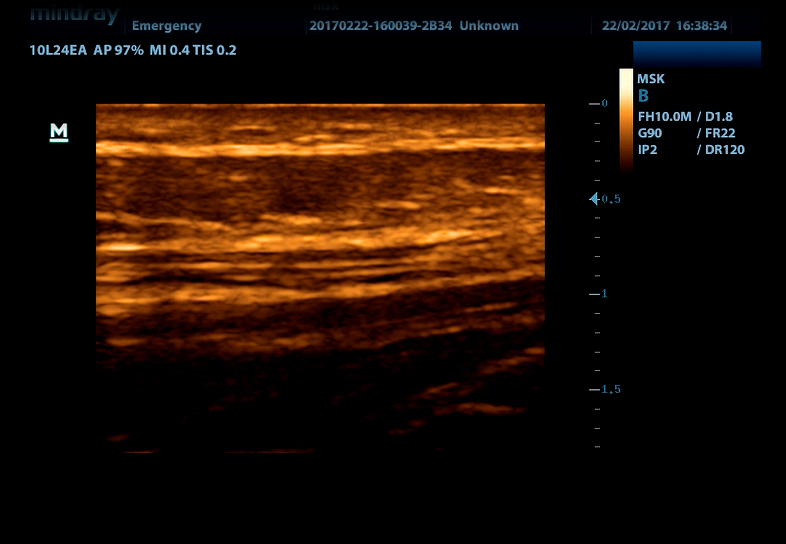

Линейный датчик высокочастотный 10L24EA (8.0/10.0/12.0/14.0/Н10.0/Н12.0 МГц, 24 мм)